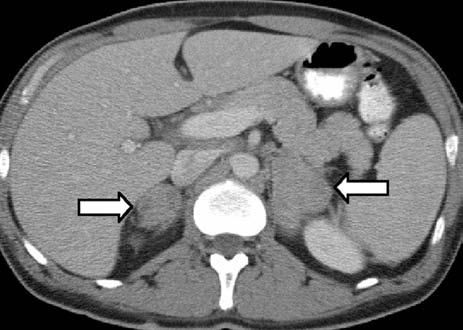

Laboratory evaluation revealed a normal complete blood cell count but mildly elevated levels of transaminases. A chest radiograph revealed a 2-cm cavitary right upper lobe (RUL) lesion (Figure 1). CT scans of the chest and abdomen revealed the solitary lung lesion, on a background of centrilobular emphysema (Figure 2), and bilateral non-homogeneous adrenal glands, with the left gland appearing larger than the right one (Figure 3). CT scans did not reveal any mediastinal lymphadenopathy or pleural effusions.

Figure 3 – Bilateral non-homogeneous densities in the adrenal glands can be seen in this abdominal CT scan (5- mm axial cuts) after oral and intravenous administration of contrast (arrows).